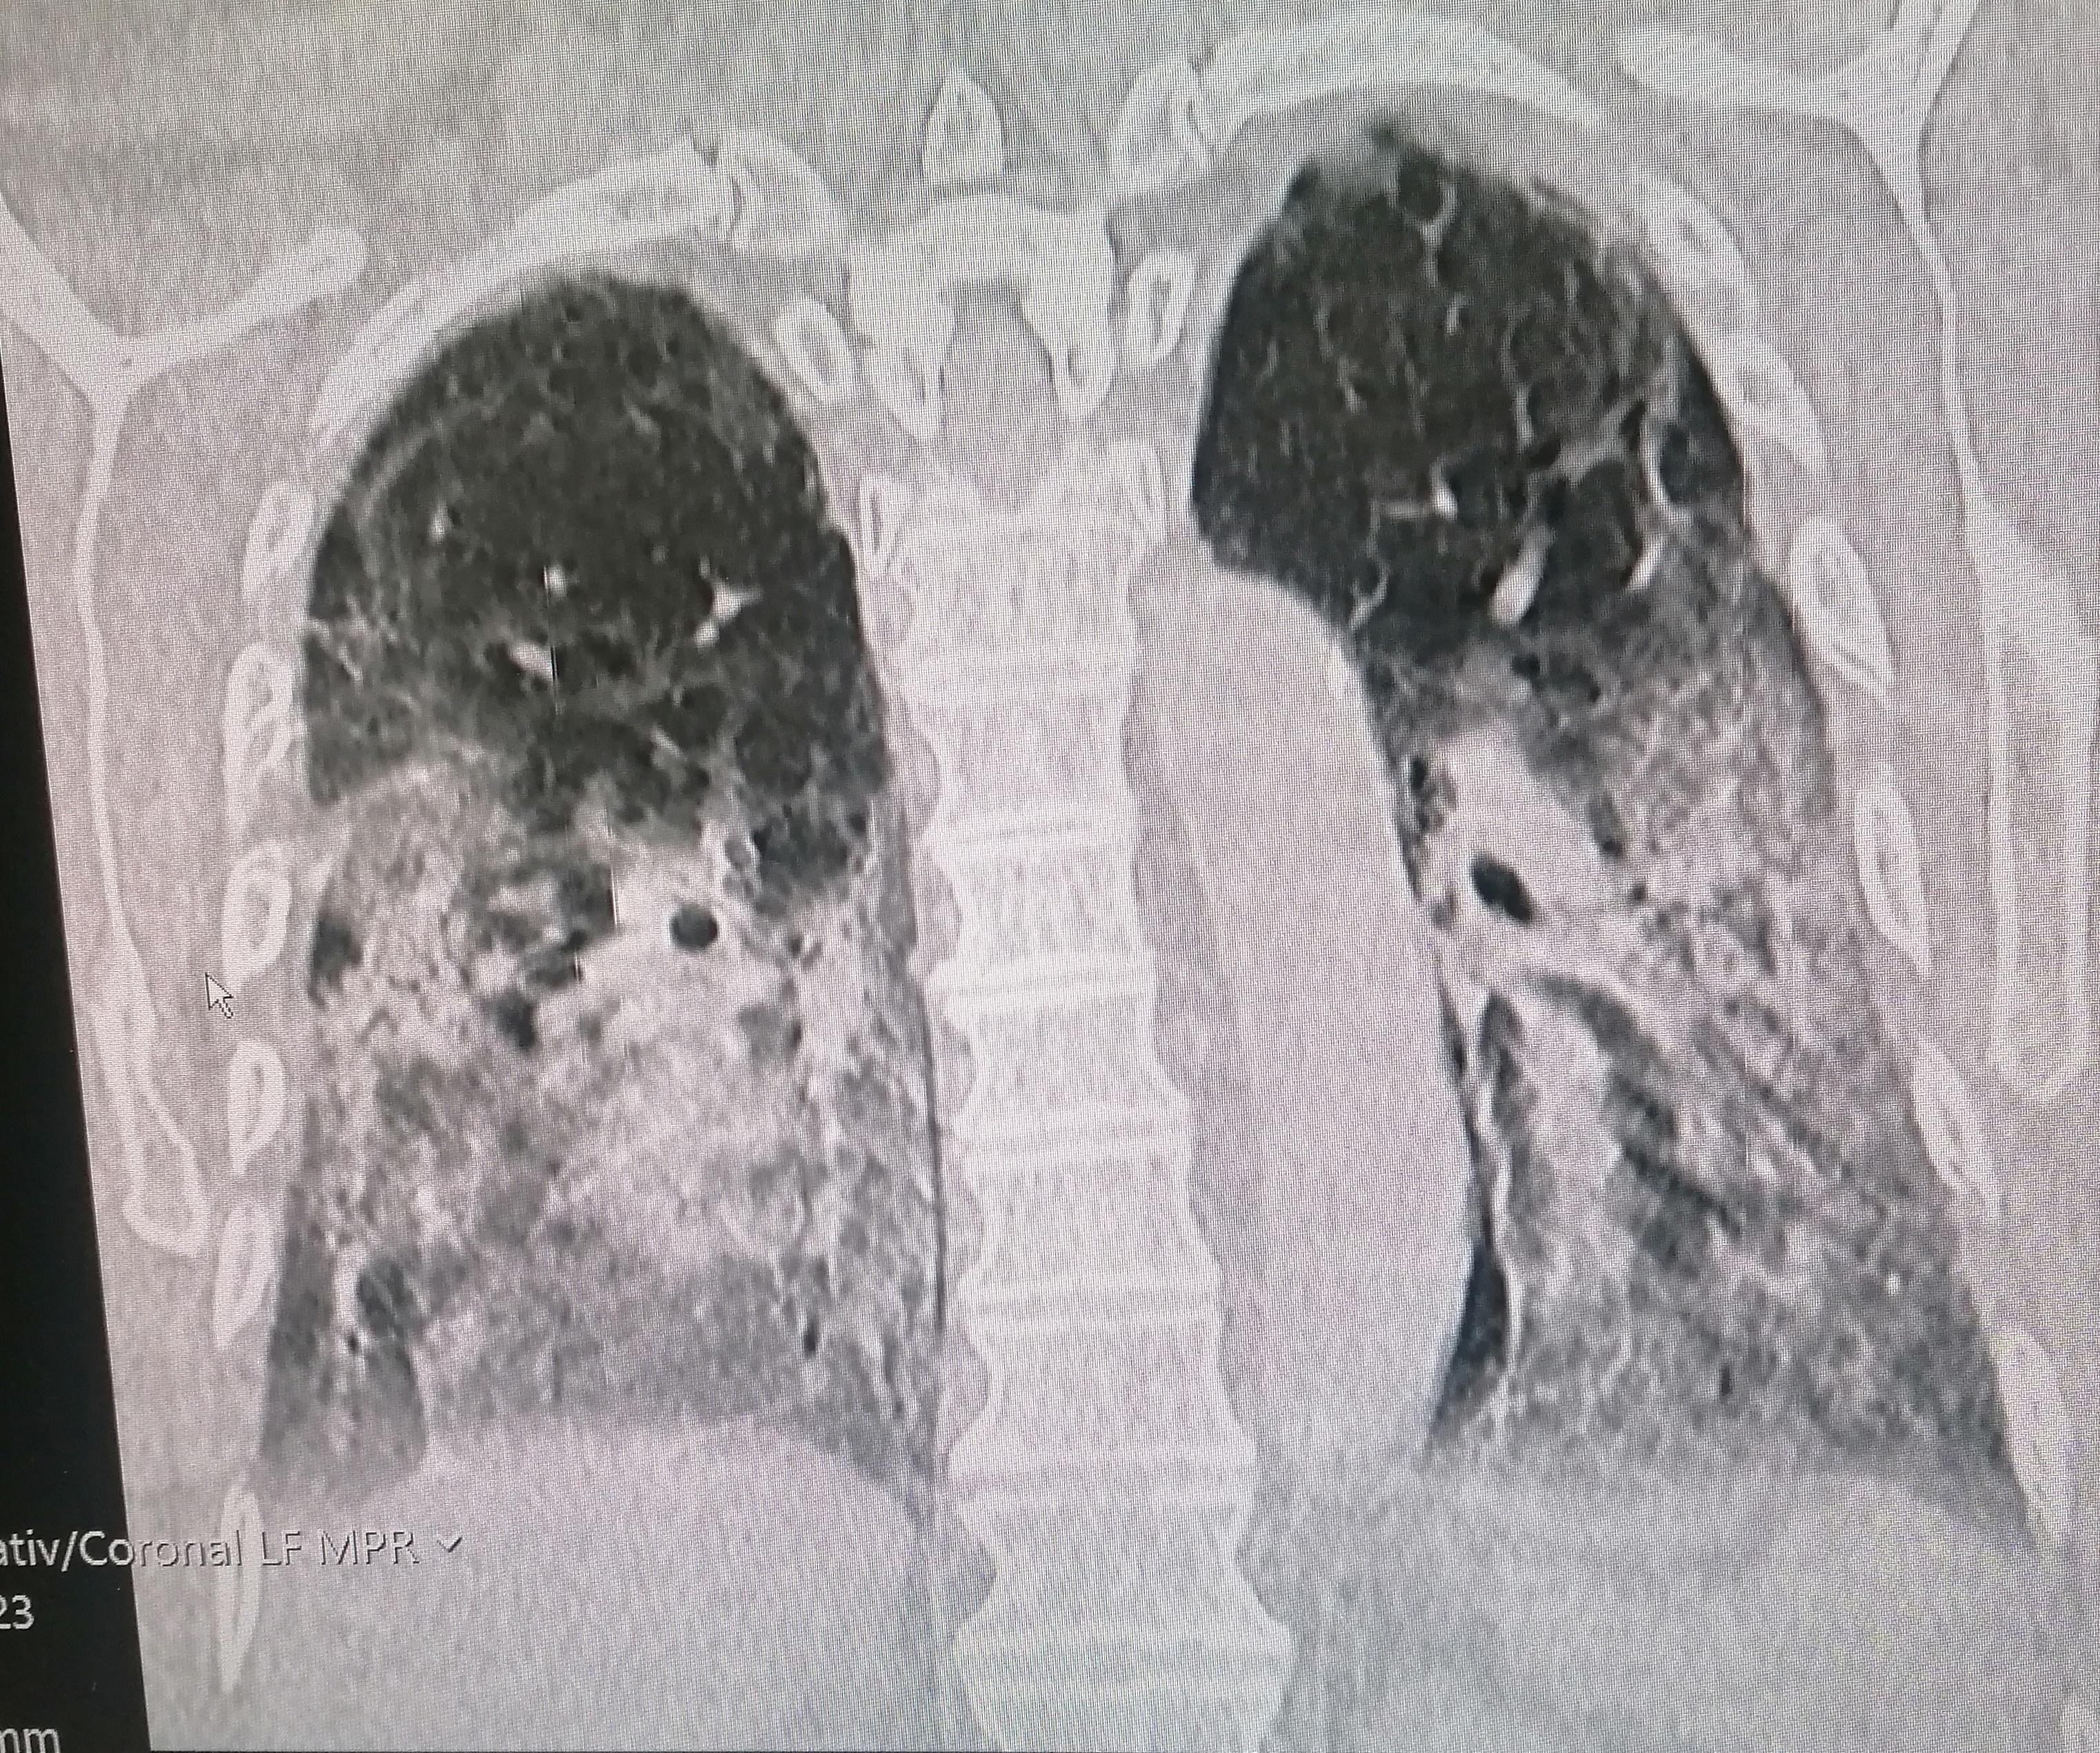

This is Covid lungs